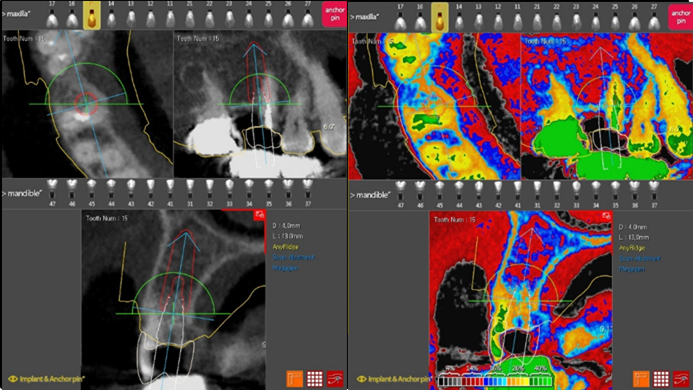

Clinical case: R2GATE GUIDE surgery with GBR

- Courtesy of Dr. Kwang Bum Park, Korea -

Dr. Kwang Bum Park, digital guided surgery, bone regeneration, maxillary posterior, #13, #14, guided surgery, GBR, AnyRidge, i-GEN, Mega-Oss, R2GATE, R2GATE Full surgical kit